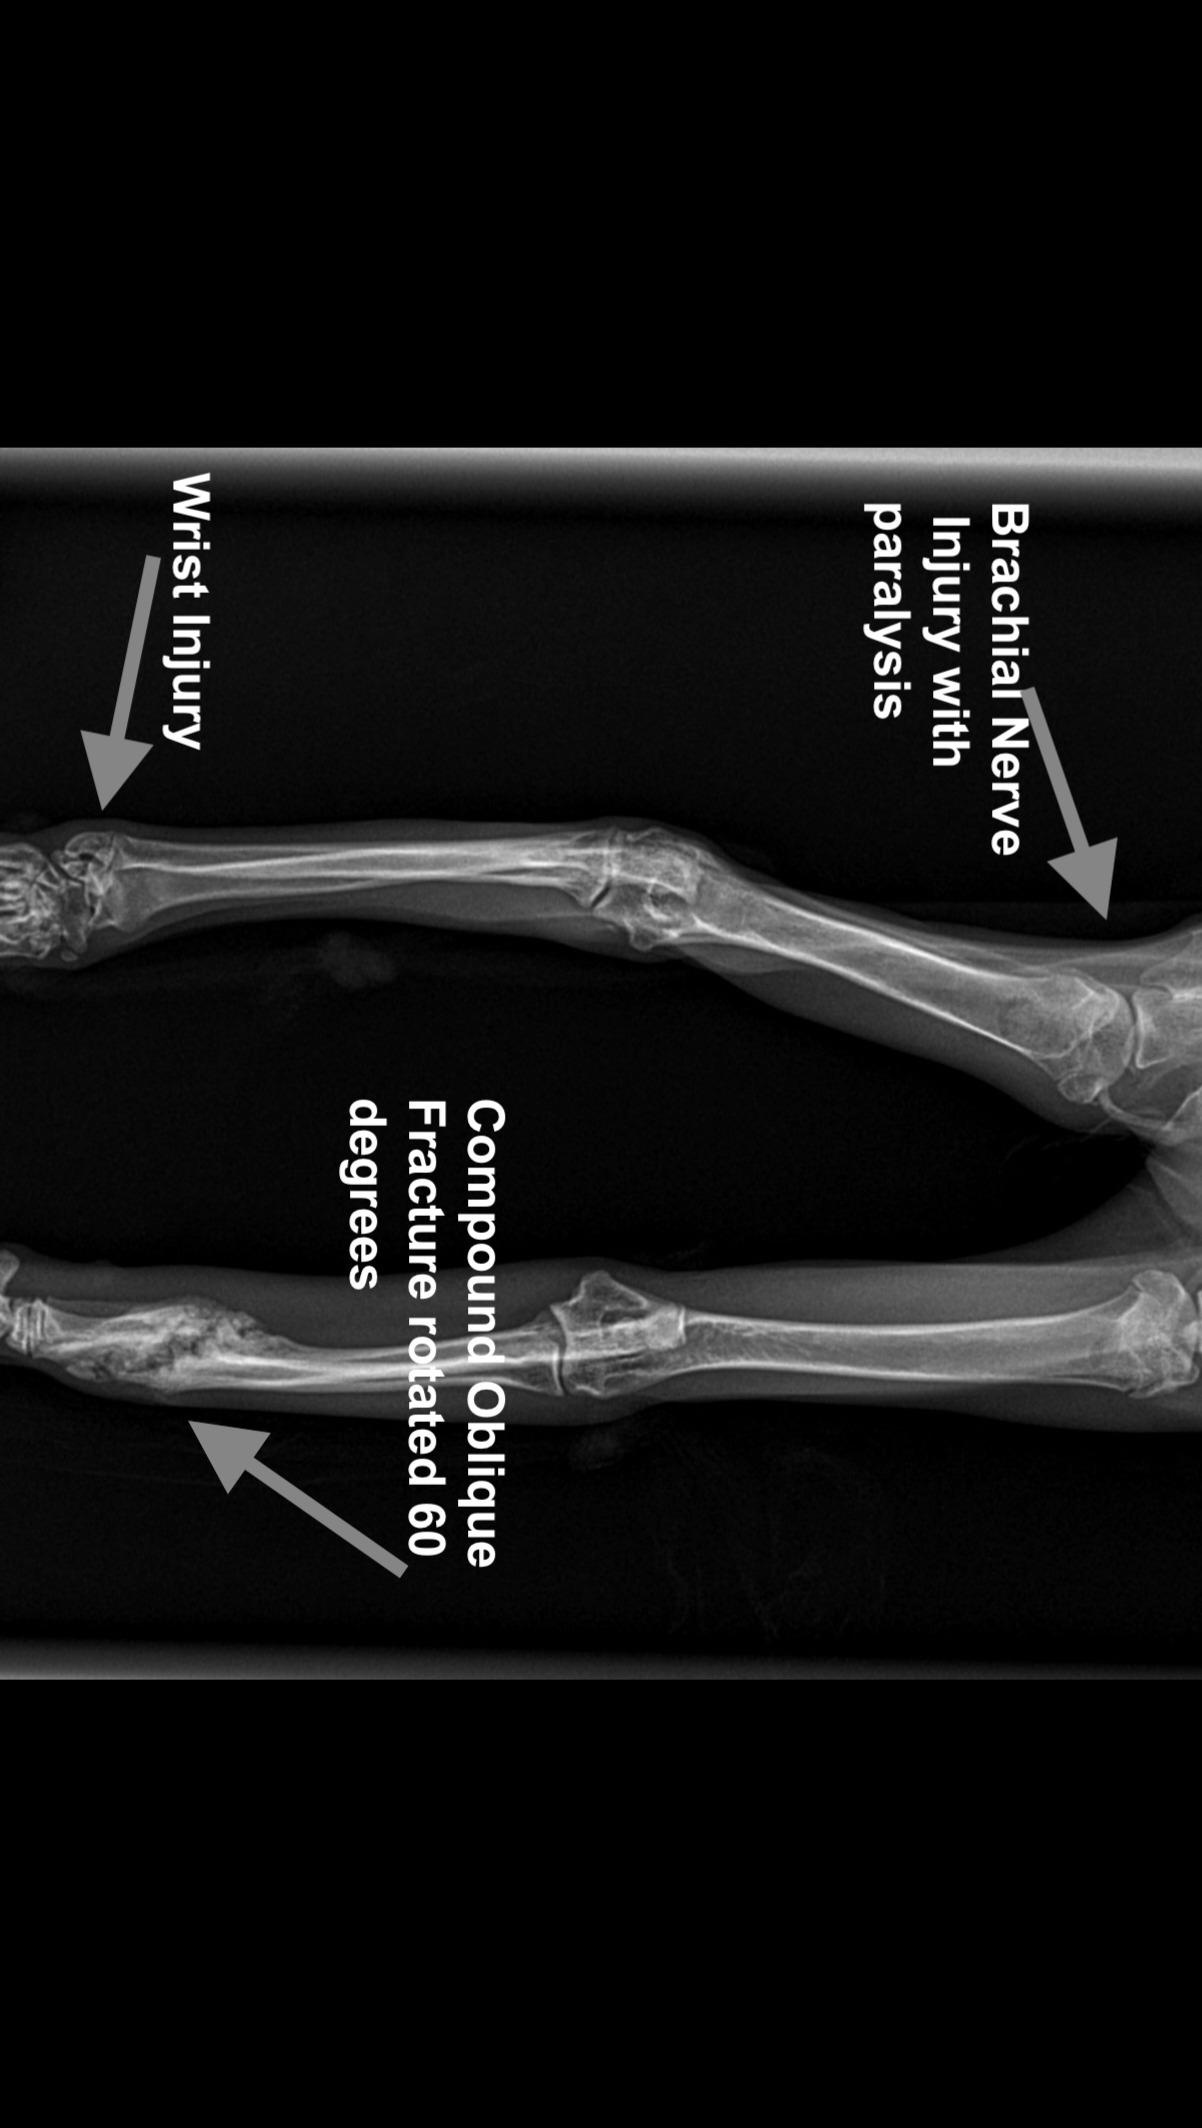

We rushed her immediately to an emergency veterinary clinic, where she weighed 3.9 lbs., about half what an eight-month-old kitten should weigh. The exam found multiple wounds from head to tail, her left leg was extremely atrophied and paralyzed with likely radial nerve damage, her left elbow was raw from pulling herself along with it, and her left wrist was also injured. X-rays showed the biggest surprise though... her "good" leg, the right front, had broken radius and ulna bones (a compound oblique fracture) from about 6 weeks prior, which had rotated 60 degrees and is healing out of alignment. It was clear that Annie had suffered traumatic injuries consistent with being hit by a car, and it happened within days of escaping more than six weeks prior.

This explained why her left elbow was scraped raw, and why she was so skinny: for six weeks her right front leg was broken and her left front leg was basically paralyzed from the elbow down, so the only way that this poor kitten could move around to find food was to drag herself using her left elbow. We have no idea how Annie was able to find food or even protect herself from feral cats and any other threats with no working front legs for six weeks. A few days later the labs came back that she also had the Giardia parasite, probably exposed at the same time as Apollo before she escaped, and she also had Hookworm.

The orthopedic veterinary surgeon is confident that once the right leg has healed completely, he can re-break the radius and ulna, realign everything properly, and reinforce it with a metal plate so she can walk normally on it. If we don’t do the surgery, he believes Annie would develop severe arthritis and other joint issues. This surgery is estimated at $6,000 to $10,000, on top of the $3,000 already paid. The prognosis for the left front leg is not as good, with amputation as the most likely outcome.

Not wanting to rush into an amputation, we began physical therapy and are trying to see what is wrong with her left front wrist in the hopes that once we fix the wrist she might be able to use the left leg again. If surgery on the wrist is needed it will likely cost about the same as the right leg surgery, plus the cost of physical therapy before and afterwards, etc. If the left wrist cannot be corrected, then the entire left leg will probably have to be amputated at the shoulder in order to prevent her from trying to chew it off (animals will often try to do this when they have a damaged limb).